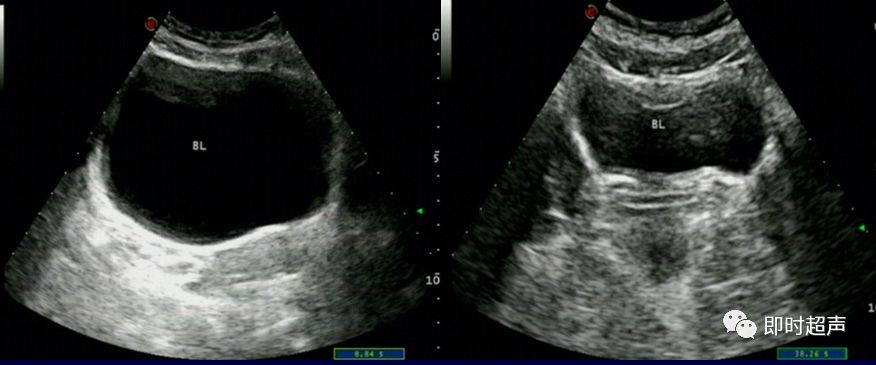

膀胱的形态大小、位置均与尿量有关

充盈良好 充盈差

- 排尿前后憩室腔大小随膀胱容量多少而改变

单发 多发

D:憩室 憩室口(箭头所示)